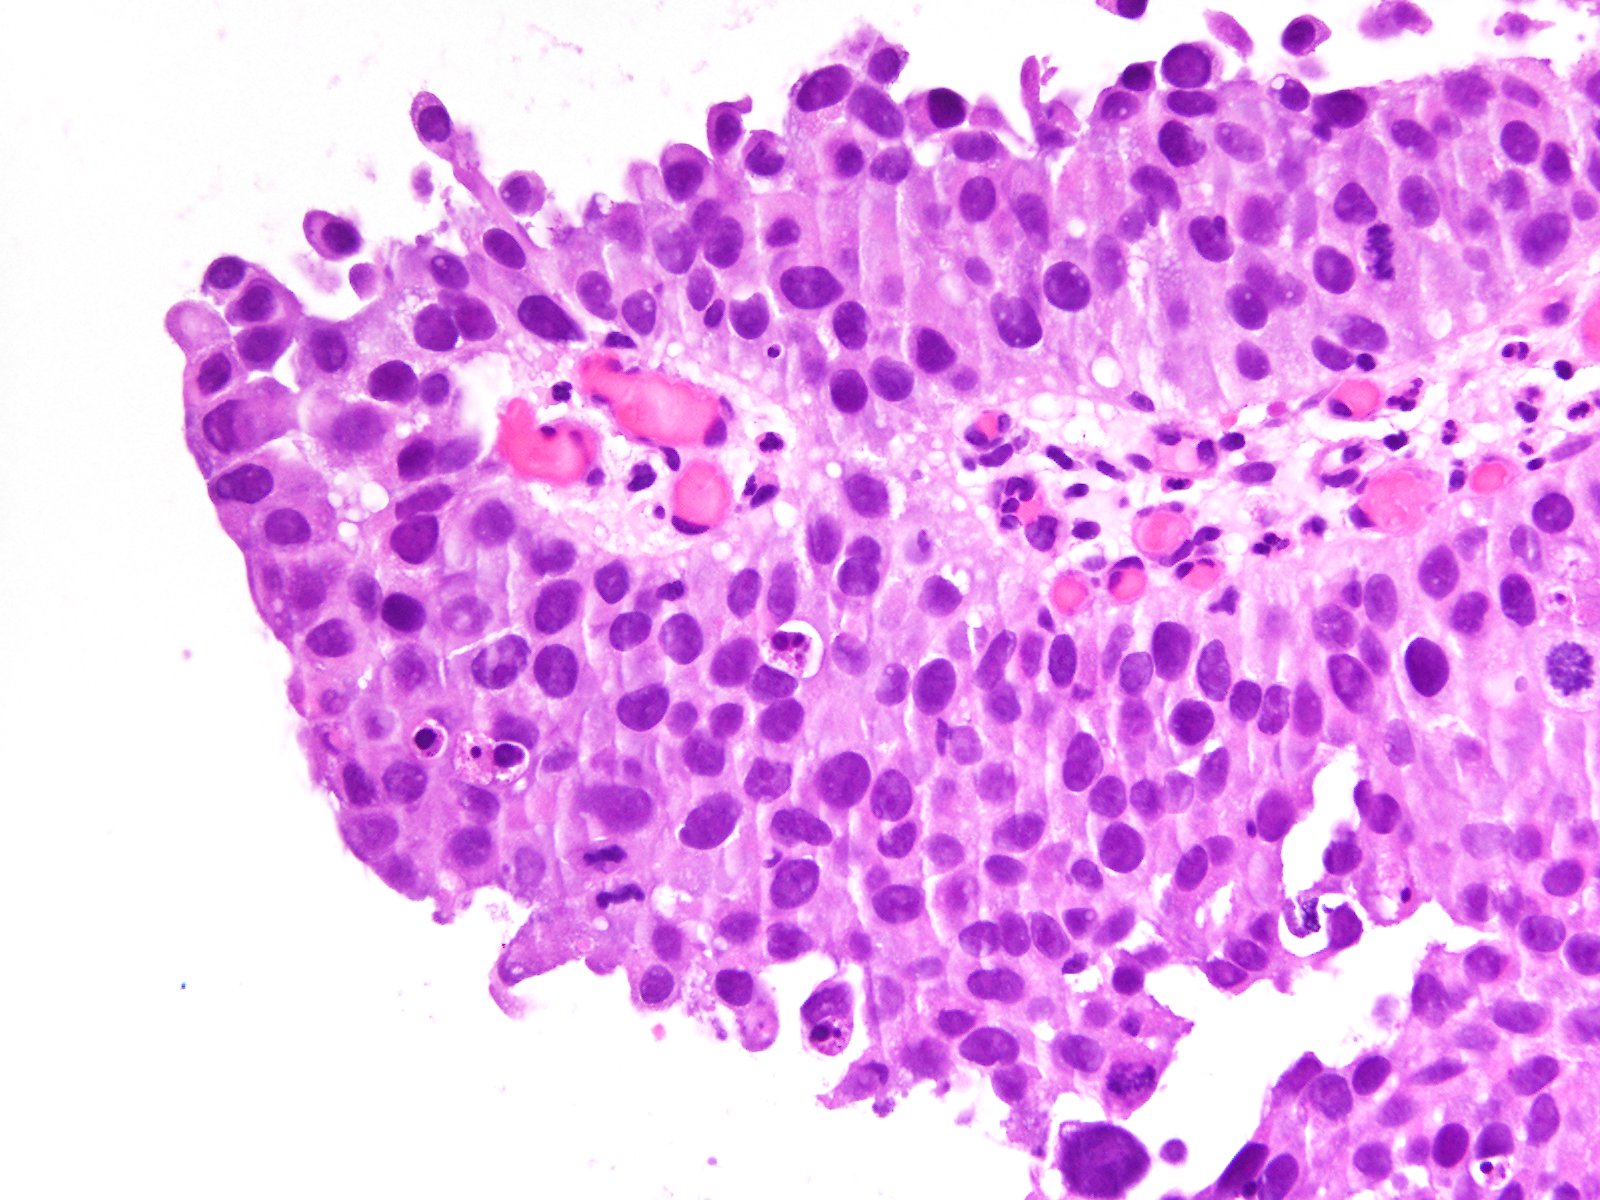

Bladder Papillary Lesions

Case ID: 363